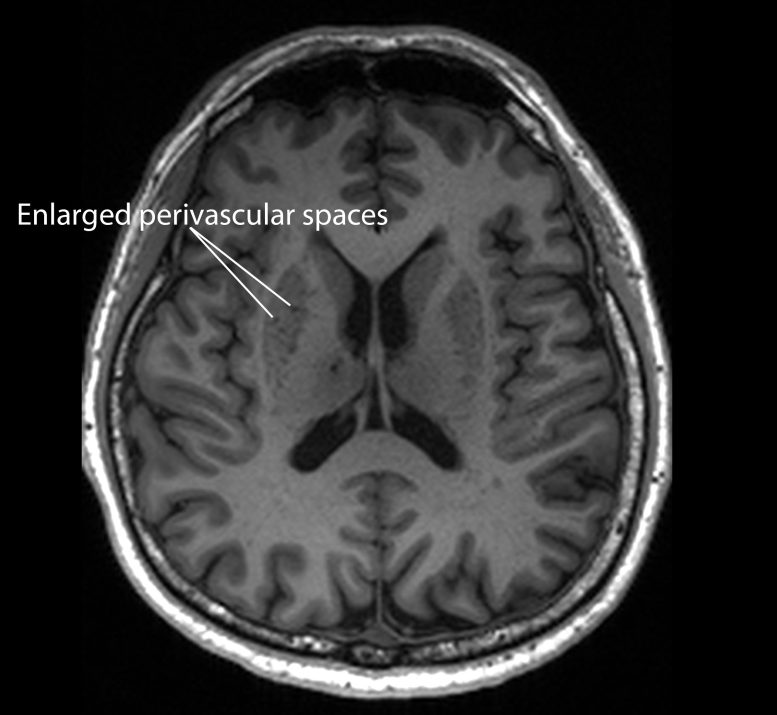

Their findings indicate that these blockages, known as “enlarged perivascular spaces”, could serve as an important early signal of Alzheimer’s, one of the most common forms of dementia.

The brain’s blood vessels are surrounded by small channels called perivascular spaces. These serve as pathways for clearing harmful waste such as beta amyloid and tau proteins, both of which appear in unusually high amounts in people with Alzheimer’s.

When this drainage system becomes inefficient, the spaces expand and form enlarged perivascular spaces that are detectable on MRI scans. However, previous studies had not fully clarified whether this phenomenon was directly associated with dementia or specifically with Alzheimer’s disease.

For the latest study, the researchers analyzed the MRI scans of the participants and found that those with mild cognitive impairment tend to have clogged drains in their brains, or enlarged perivascular spaces, compared to the other participants.